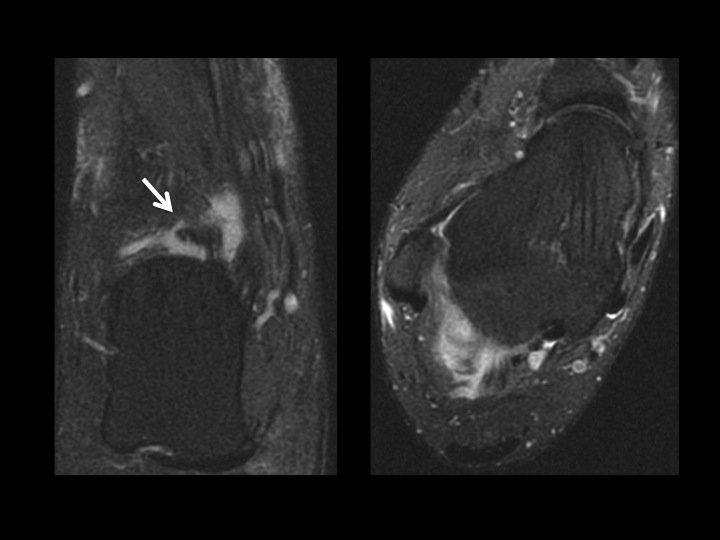

There is an accessory articular facet of the medial talus posterior to the middle facet, with non-osseous extra-articular talocalcaneal coalition (slides 1-2). In slide 3 there is an accessory ligament Ive not seen connecting the lateral tubercle of the posterior talar process and the posterior calcaneal tubercle, with surrounding synovitis (slide 4); does this have a name? As a side question, is there a consensus as to what the cyst-like changes are deep to the angle of Gissane in the calcaneus? Do you all report this? I consider this incidental, does anyone disagree?